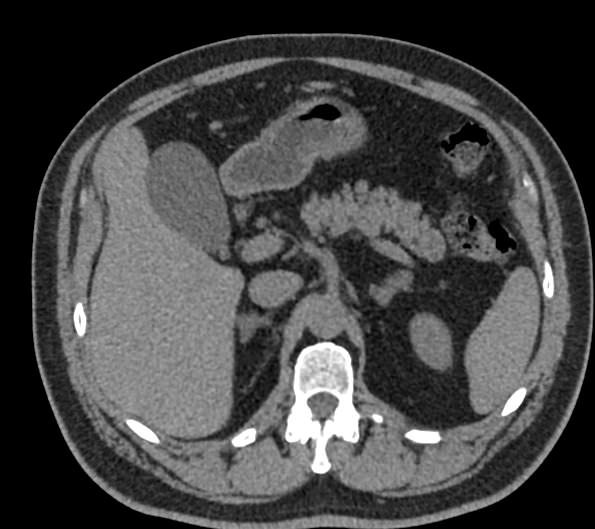

Современным высокоинформативным способом выявления патологических изменений поджелудочной железы является мультиспиральная компьютерная томография с прицельным сканированием органа.

При помощи специальных цифровых приложений данные, полученные при сканировании, преобразуются в трехмерные изображения органа, что дополнительно повышает точность и достоверность диагностики заболеваний поджелудочной железы.

Контрастирование позволяет отличить зоны воспаления, деструкции, разрастания фиброзной ткани и опухолевой трансформации от сохраненной паренхимы поджелудочной железы. КТ поджелудочной железы с контрастированием дает исчерпывающую информацию о состоянии органа и патологических процессах в нем.

Что покажет КТ поджелудочной железы

- злокачественные и доброкачественные опухоли, включая инсулиному, глюкагоному, випому, гастриному, рак поджелудочной железы;

- кальцинаты в панкреатических протоках;

- острую и хроническую формы панкреатита;

- кисты и псевдокисты поджелудочной железы